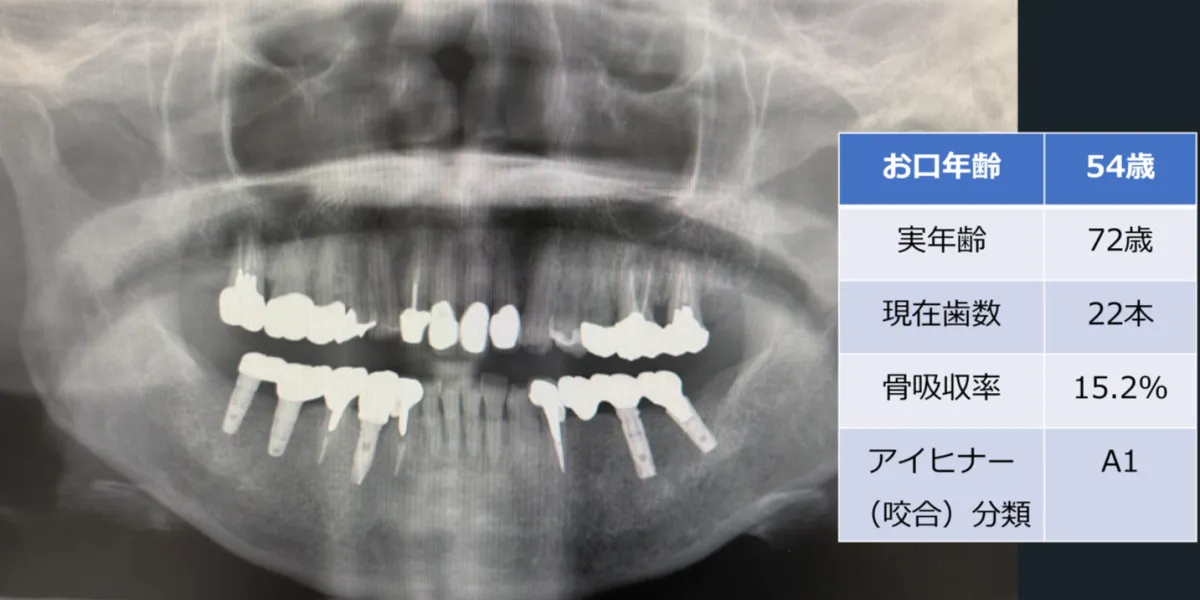

このシステムは、エックス線画像から複数のデータを抽出します。具体的には、現在の歯数、インプラント数、咬合状態、歯槽骨の吸収量などを詳細に分析し、患者の生年月日や性別と組み合わせて「お口年齢」を算出します。これまでの「歯科パノラマエックス線画像を用いた歯科健診システム」を進化させ、誰でも簡単に情報を得られるような設計がされています。

さらに、このシステムでは画像の元データを必要とせず、ディスプレイに映されたエックス線画像をスマートフォンで撮影した写真からも認識できるため、従来の方法に比べて大幅に利便性が向上しています。